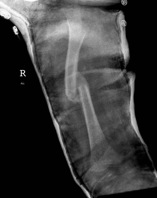

Management 12 years and over

Issues

1. Less potential to remodel (especially > 10)

2. Usually too heavy for flexible nails

3. Risk of AVN with standard nails

Options

1. Flexible nails

- < 50 kg

2. Plate

3. Antegrade Lateral Entry Trans-trochanteric Femoral Nail

Keeler et al. J Paediatr Orthop 2009

- 80 femoral fractures treated with lateral entry femoral nails

- no AVN

- no malunion or nonunion